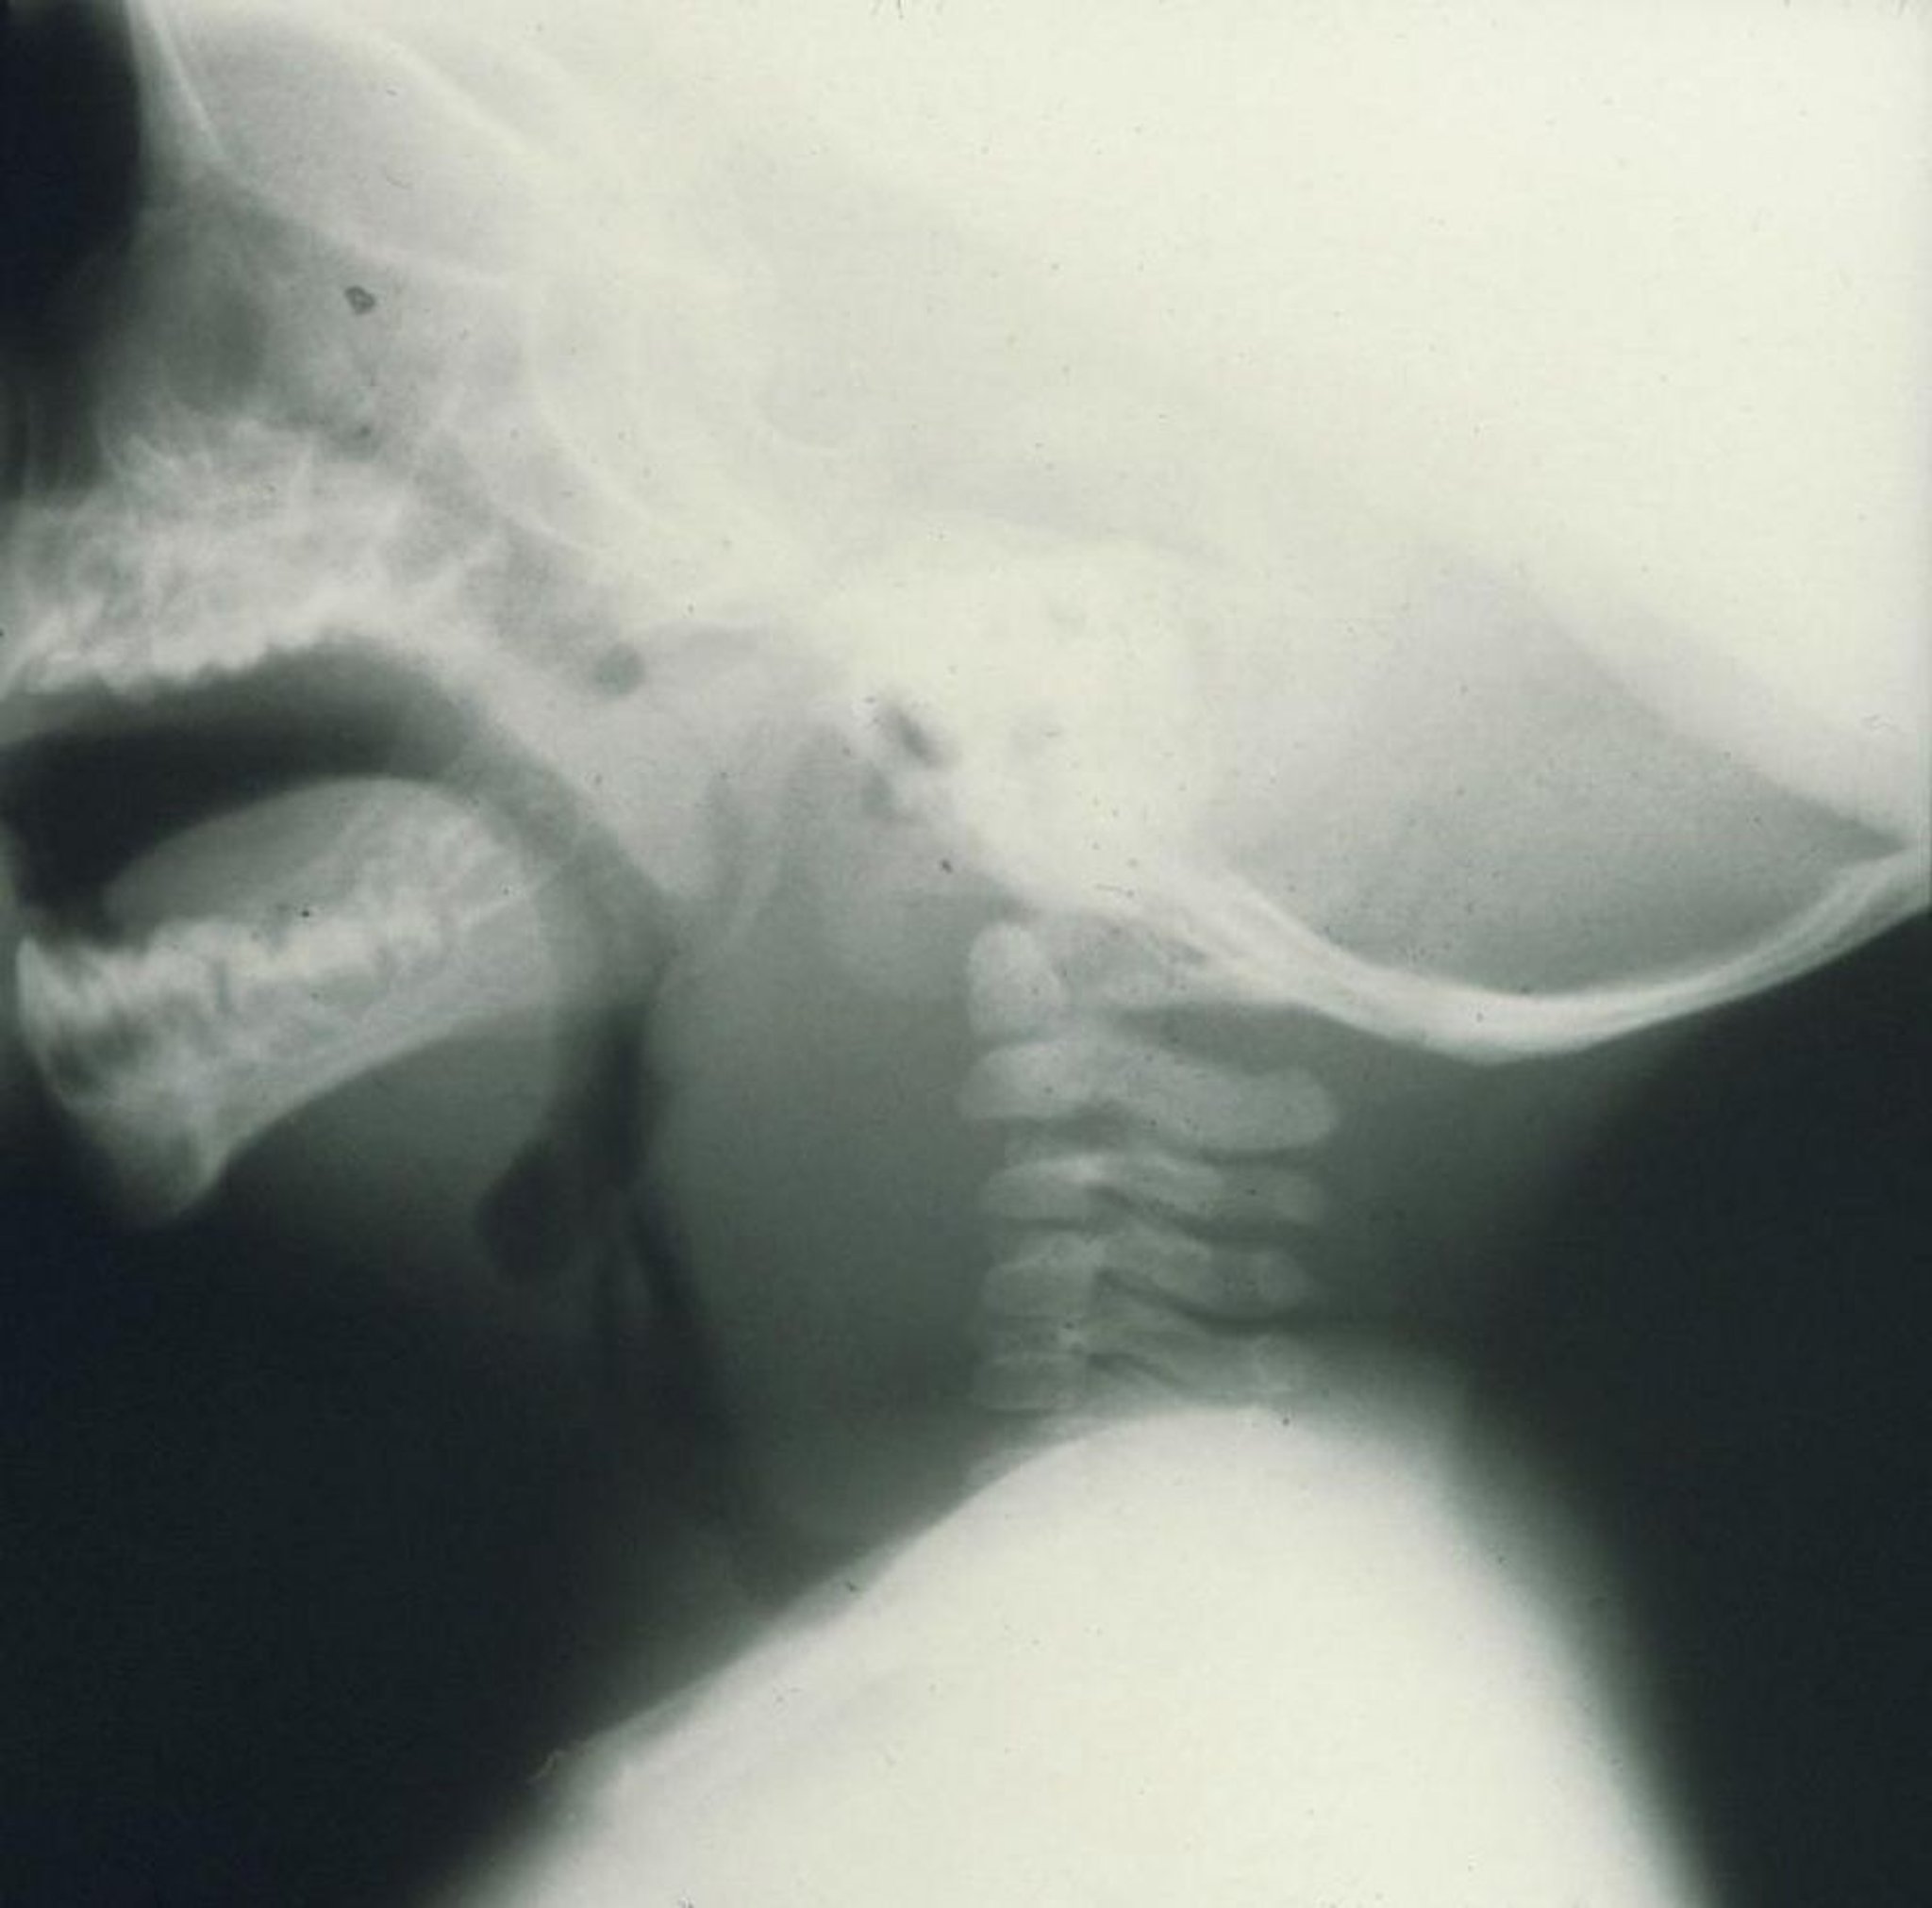

Ascesso retrofaringeo

Questa radiografia di profilo di un bambino mostra un marcato gonfiore anteriore alle vertebre cervicali causato da un ascesso retrofaringeo.

Image provided by Clarence T. Sasaki, MD.